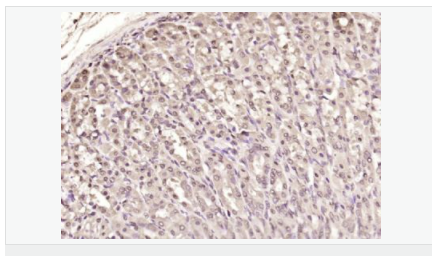

Rabbit anti- phospho-IKB alpha (Tyr305) Polyclonal antibody

英文名稱phospho-IKB alpha (Tyr305)

中文名稱磷酸化IKB alpha抗體

產品應用WB=1:500-2000 ELISA=1:5000-10000 IHC-P=1:100-500 IHC-F=1:100-500 Flow-Cyt=1μg/Test ICC=1:100 IF=1:100-500 (石蠟切片需做抗原修復)